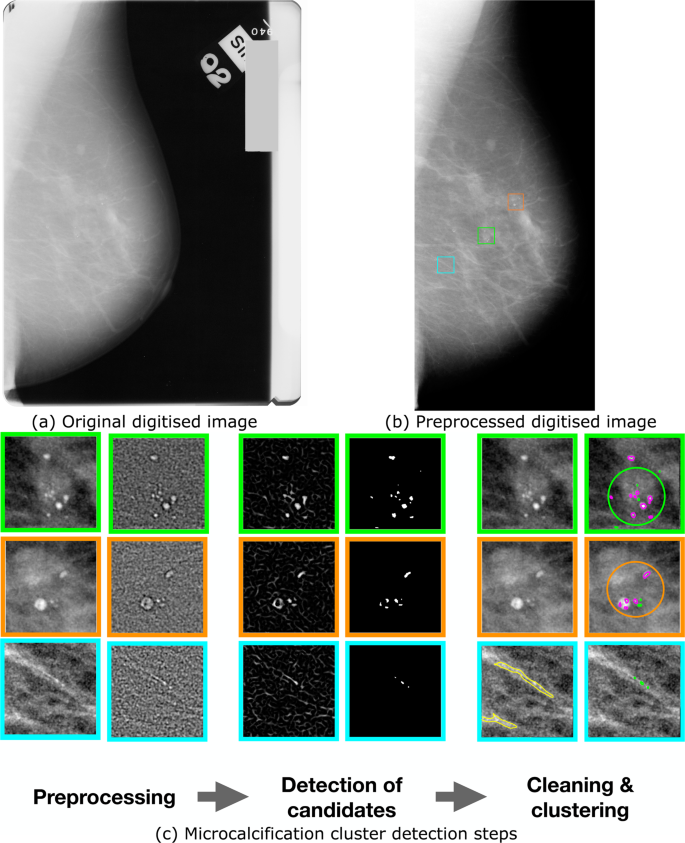

They appear as white spots or flecks on a mammogram but can't be felt during a breast exam. A new group has formed. For women treated for breast cancer in the past, calcifications may also be due.

There are numerous causes for calcium deposits in the breasts, including: But, japanese food natto has the ability to decalcify and maintain uniform level of calcium throughout the body and parts. Breast calcifications. california pacific medical center:

There are a significant number. This is especially good for. Calcifications in a noncancerous growth called a fibroadenoma.